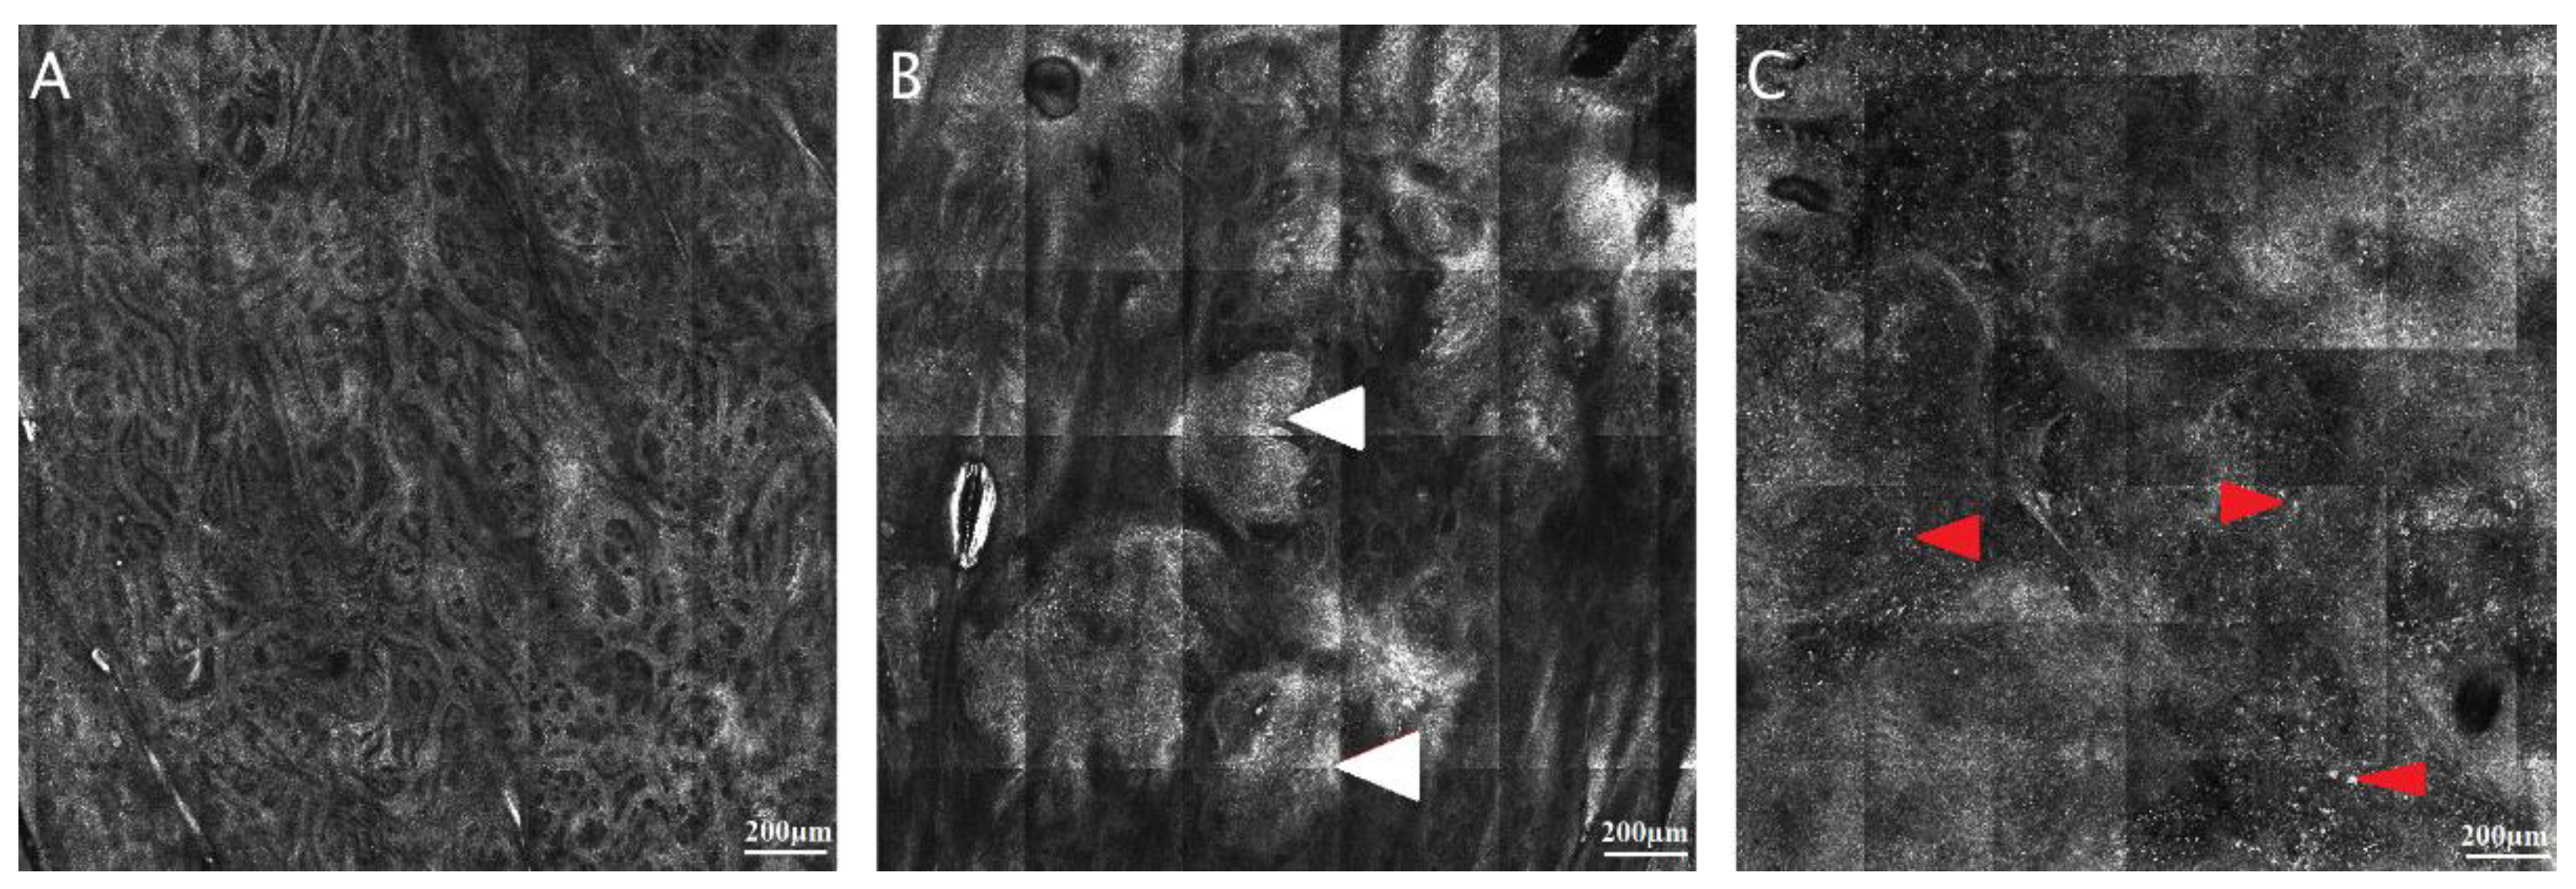

3.2. Automated Delineation of the Dermal-Epidermal Junction

3.3. Convolutional Neural Networks and Classification and Regression Trees for Skin Lesion Identification on Static RCM Images